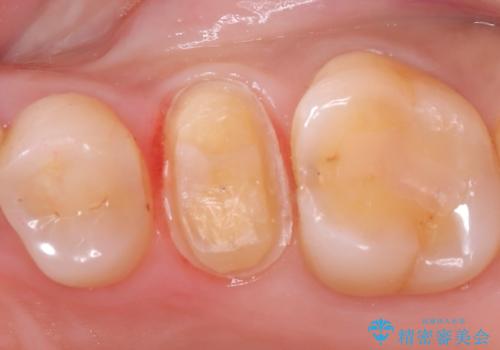

- 銀歯をやり替えたいとのことでした。残っている歯の量や長期的な予後をふまえ、患者様との相談の結果、被せ物での修復となりました。

メタルインレーを除去し、その下にあったう蝕を除去したうえで、CRにて築造を行い形成しました。印象時は圧排し、シリコンにて精密に行っています。